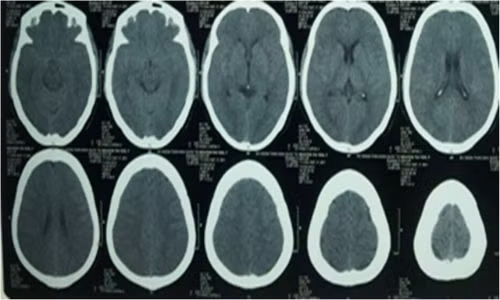

Theo các bác sĩ Bệnh viện đa khoa huyện Mê Linh, 1ua quá trình điều trị và làm các xét nghiệ : Chụp cắt lớp vi tính, sọ không tiêm thuốc cản quang, độ dày lát cắt 4mm tầng dưới lều và 8 mm tầng trên lều. Siêu âm ổ bụng gan, mật tụy, lách, thận, bang quang. Bệnh viện đã tiến hành mở khí quản cho bệnh nhân tại khoa Hồi sức cấp cứu.